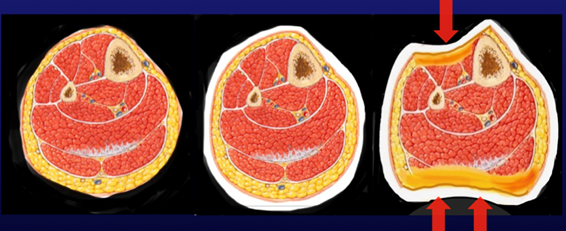

Sarmiento y sus colaboradores en 1970 analizaron una serie de 1000 pacientes con fracturas diafisarias de tibia a los que se le realizó tratamiento funcional; incorporando el concepto de que el apoyo temprano mejora los resultados en cuanto a consolidación y función del miembro afectado. Las principales ventajas que se desprenden de este tratamiento son que acelera el proceso de consolidación, con un bajo índice de retardo de consolidación y pseudoartrosis, previene la rigidez articular y atrofia muscular; lo que lleva a una recuperación mas rápida luego de la inmovilización así como mayor libertad durante período de curación7. Todos estos beneficios parten de los dos principios fundamentales del tratamiento funcional de las fracturas, que son el estímulo funcional precoz y la movilidad controlada del foco fracturario. El estímulo funcional no se limita solamente a la movilidad temprana de las articulaciones vecinas, sino también a la carga en el eje del hueso fracturado como principal elemento estimulador de la osteogénesis; en cuanto a la movilidad del foco de fractura con el apoyo, es fundamental que sea “controlada” ya que si ocurren movimientos exagerados, estos perjudicarían el proceso de consolidación, el cual es un proceso sobretodo vascular, donde estos movimientos exagerados impedirían el punteo de los vasos a nivel de la brecha ósea, conduciendo a la pseudoartrosis. Se puede controlar la movilidad en el foco de fractura si la columna ósea está inmersa en un ambiente de compacidad uniforme. Significa que las partes blandas que rodean a la diáfisis ejercen la misma presión a su alrededor. Para que esto ocurra no debe haber una afección importante de las partes blandas y debemos confeccionar un yeso que equipare las presiones que rodean al hueso. El yeso conformado tiene que deformar la anatomía del miembro para lograr la compacidad uniforme y así evitar los desplazamientos que pudieran ocurrir con el apoyo durante la marcha. Un ejemplo de esto es la compresión de la masa de los gemelos y el espacio interóseo en las fracturas de pierna10,11,14. Figura 2.

Figura 2: A) Ilustración corte axial de pierna B) Yeso convencional respetando anatomía C) Yeso conformado de pierna deformando anatomía para lograr compacidad uniforme